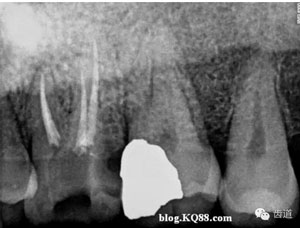

遞氧化鋅丁香油糊劑暫封,囑病人去放射科拍x線片